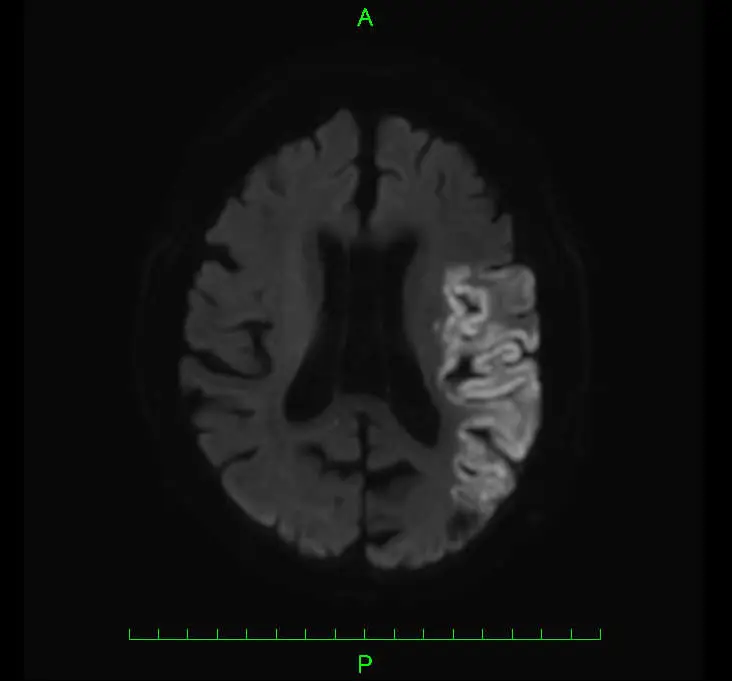

主に頭部MRI検査および頭部CT検査を用います。CTやMRIで脳梗塞と診断された場合は、原因の特定等を目的に心臓超音波検査や頸動脈超音波検査、心電図検査などを行います。

脳梗塞(のうこうそく)とは、脳の血管がつまることにより脳にダメージが発生する病気の総称です。心臓や他の血管で出来た血栓(血のかたまり)が流れてきてつまる脳塞栓症や、動脈硬化により徐々に血管が狭くなって最終的に詰まる脳血栓症などがあります。血管がつまって血流が阻害されると、そこから先に栄養がいかなくなるため脳の組織に障害が発生します。脳のダメージは発症から数時間で発生し、早急に血流を再開させないと不可逆的な(元に戻らない)障害となるため、一刻も早い治療開始が極めて重要となります。